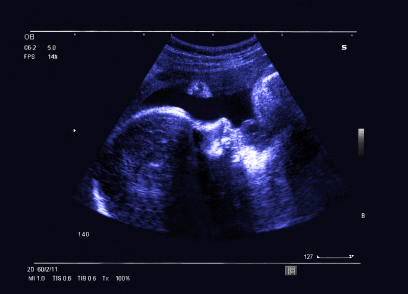

The device allows pregnant women to perform ultrasound scans at home and is connected to the user's smartphone. Exam directions are provided via an app, and are interpreted remotely by physician readers, the company said. It is already in use in Israel, Europe, Brazil, and Australia.